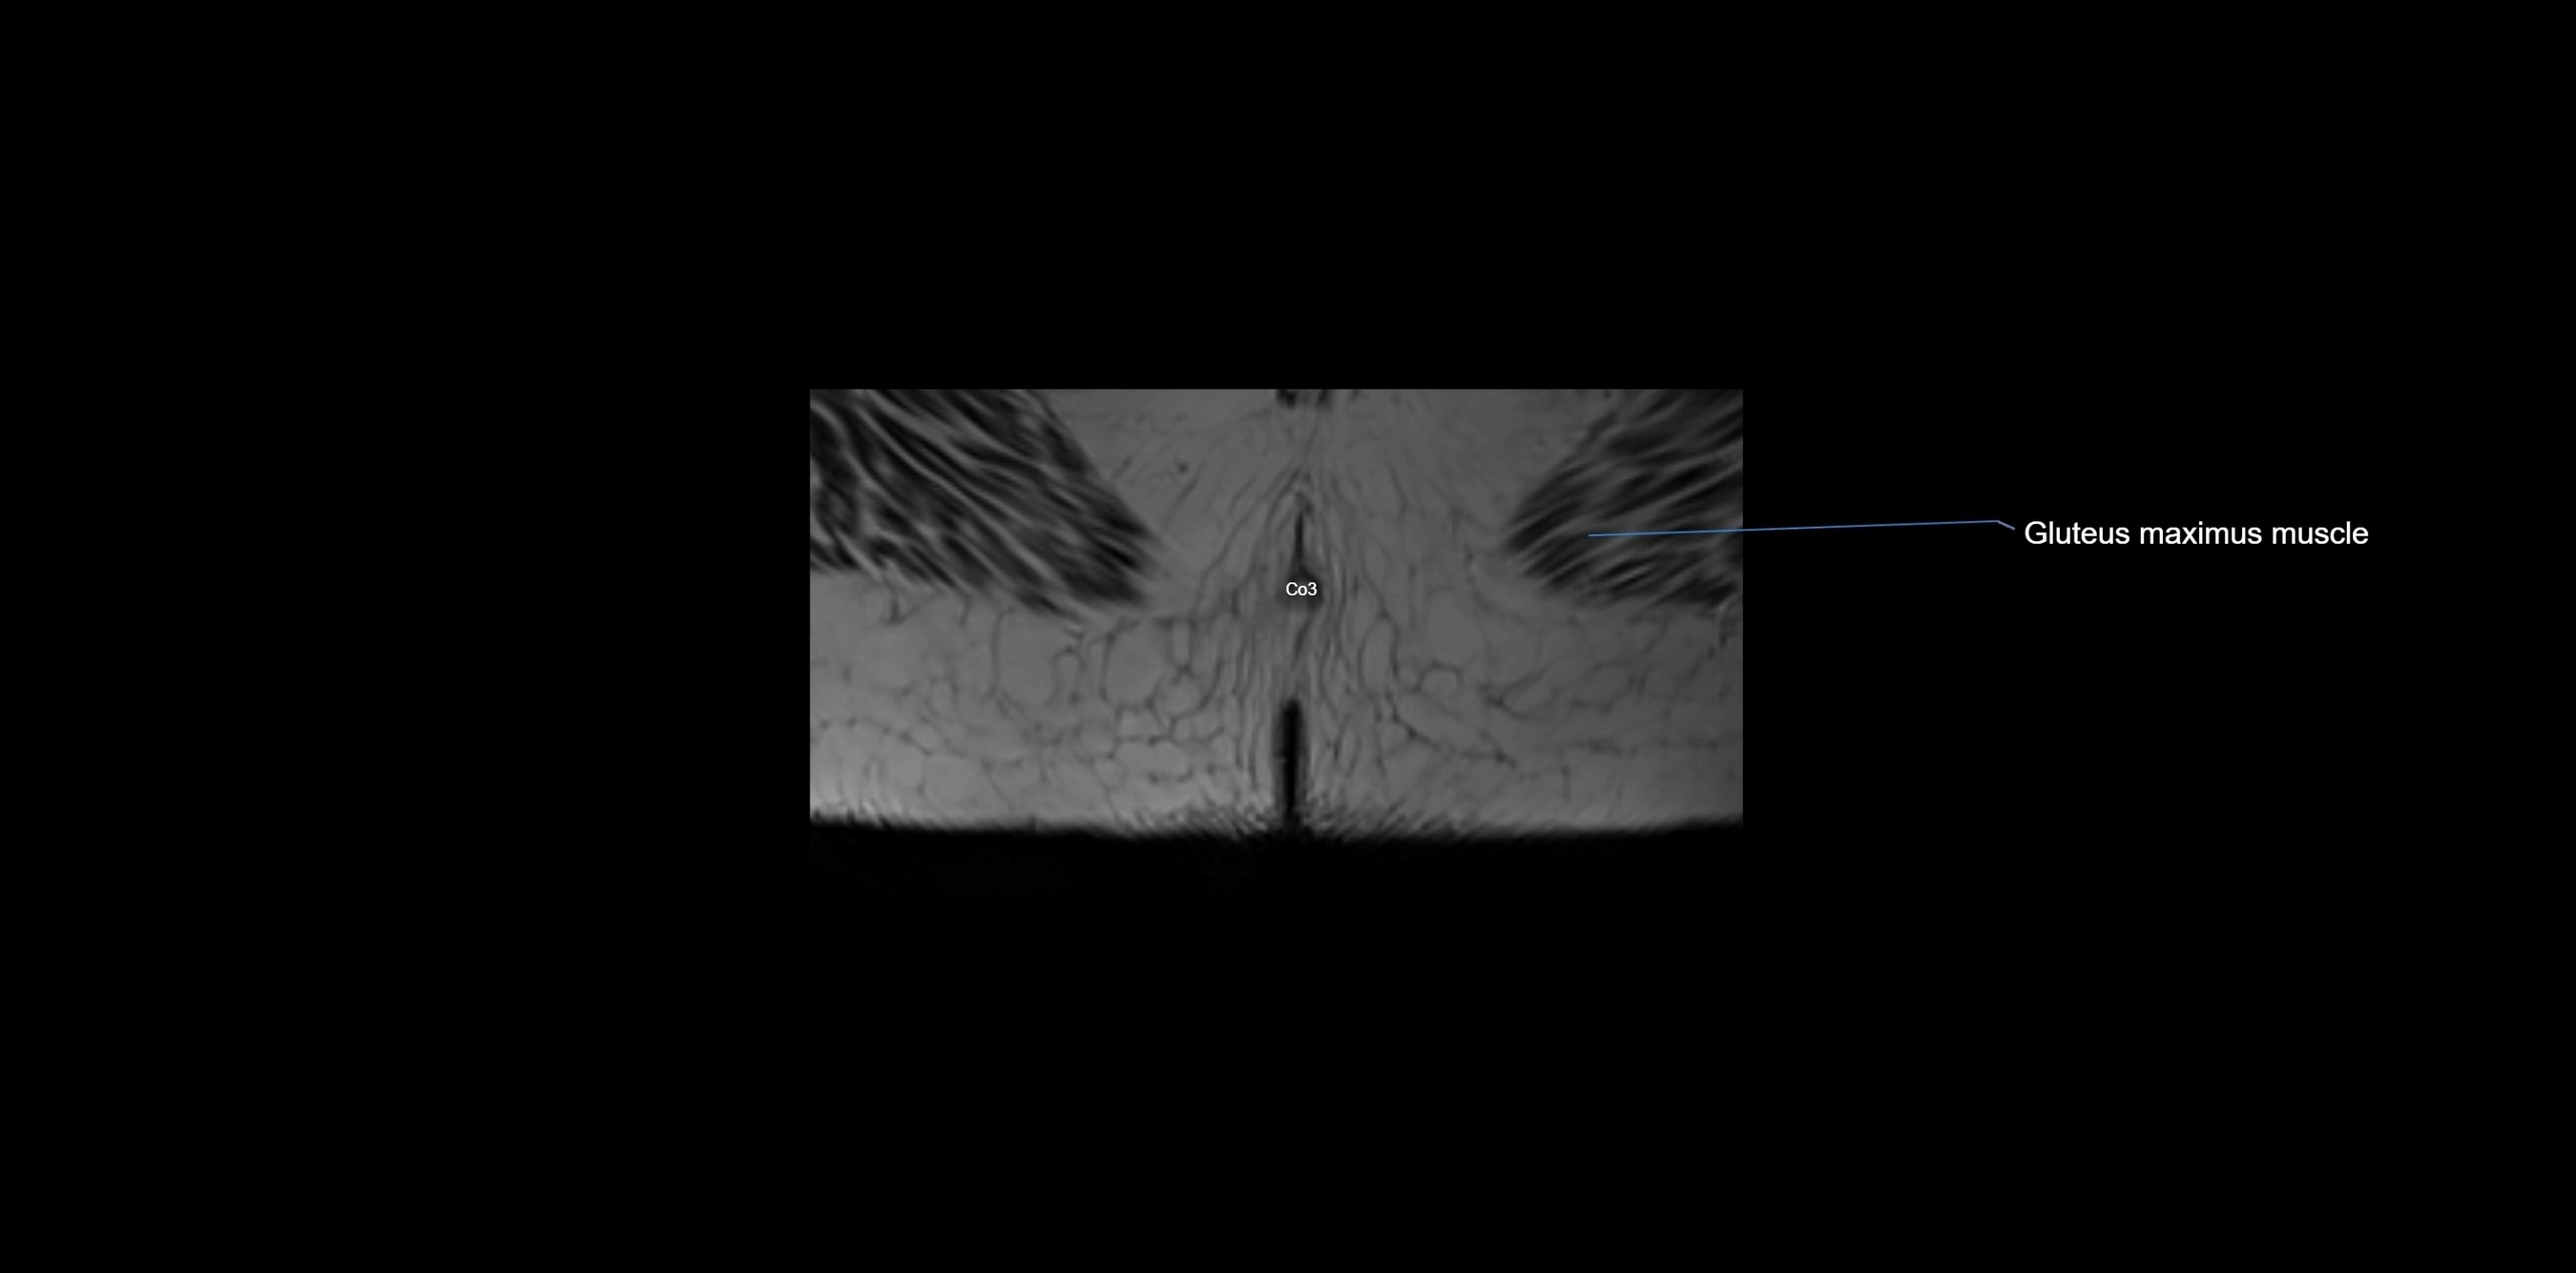

MRI image

image